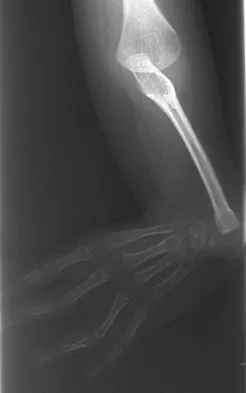

A 45-year-old man reports right shoulder pain with overhead activities only. Figures 47a through 47d show the radiographs, bone scan, and MRI scan of a lesion of the proximal shoulder. What is the most appropriate treatment?

Explanation

The figures show a lesion of the proximal humerus consistent with an enchondroma. The lesion is calcified on the radiographs. There is no cortical destruction, significant endosteal scalloping, or soft-tissue mass. The bone scan shows mild uptake in the area of the proximal humerus, and the T2-weighted MRI scan shows a lesion with high uptake, suggesting a lesion with high water content. A CT scan could also be obtained to rule out bone destruction or periosteal reaction. Pain with overhead activities is likely related to the rotator cuff. A biopsy is unlikely to add information because of inherent difficulties interpreting low-grade cartilaginous lesions. Curettage and grafting and en bloc resection are excessive treatments for a benign lesion that is apparently asymptomatic. Observation with a follow-up radiograph in 3 to 6 months is appropriate. Menendez LR (ed): Orthopaedic Knowledge Update: Musculoskeletal Tumors. Rosemont, IL, American Academy of Orthopaedic Surgeons, 2002, pp 103-111.